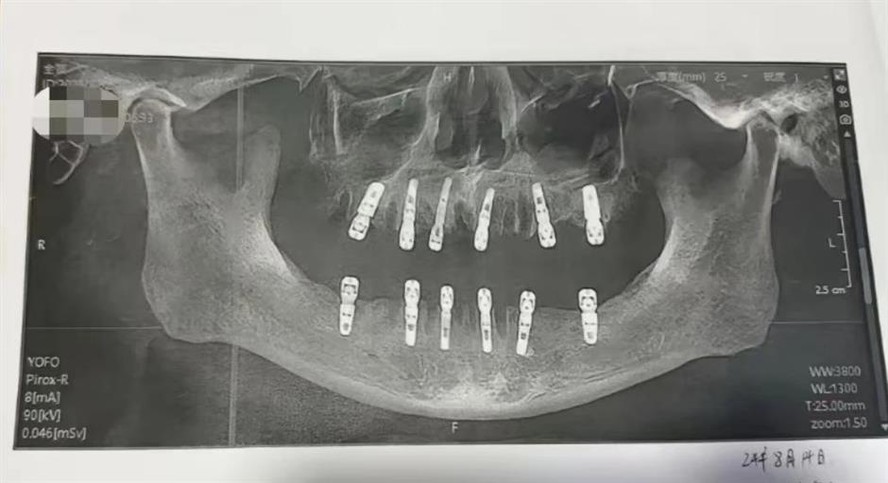

Chinês morre após passar por cirurgia invasiva — Foto: ReproduçãoUm homem morreu após passar por uma cirurgia em que teve 23 dentes extraídos e 12 implantados. O ocorrido motivou uma investigação pela Comissão de Saúde da cidade de Yongkang, província de Zhejiang, segundo o jornal chinês Shangai Daily.

O homem, identificado como Huang, passou pelo procedimento na Clínica Odontológica DeWay no dia 14 de agosto e morreu de ataque cardíaco 13 dias depois. Em seu termo de consentimento, indicou que a cirurgia envolveu a remoção de 23 dentes e a implantação imediata de 12 novos. O método é conhecido como "restauração imediata".

No entanto, o termo de consentimento de Huang mostra que vários molares foram extraídos e implantados no mesmo dia, o que quebra o procedimento usual do hospital. Segundo o Shanghai Daily, a Comissão de Saúde disse: "como houve um intervalo de 13 dias entre o procedimento e a morte de Huang, ainda estamos investigando a causa." O conselho também confirmou que a clínica é uma instituição privada com fins lucrativos, especializada em implantes dentários e endodontia.